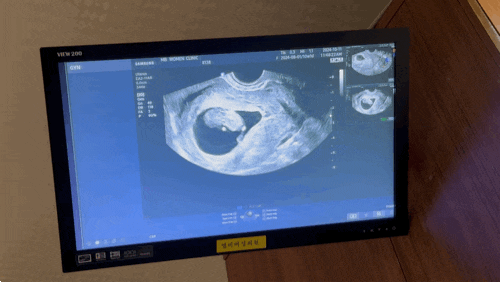

자궁경부무력증 검사 & 예방맥 수술 상담후기 (임신 13주차)

자궁경부무력증 검사 예방맥 수술 상담 후기 1) 맥수술 전문 병원 2) 대학병원급 여성병원 임신 초기 부터 ...

임신 9주 자궁경부 무력증 의심

임신 초기 출혈, 원인을 찾다 (1) 임신초기 5주부터 출혈이 계속 되었다. 계속되는 출혈에 주위에 쉽사리 ...